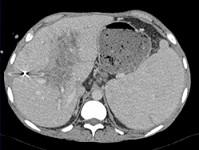

下列图像最可能的诊断是 ( )A.脂肪肝B.肝囊肿C.肝血管瘤D.肝脓肿E.肝炎肝硬化

问题 下列图像最可能的诊断是 ( )

选项 A.脂肪肝 B.肝囊肿 C.肝血管瘤 D.肝脓肿 E.肝炎肝硬化

答案 D